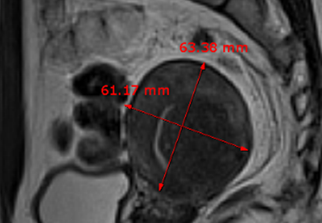

자궁근종 비수술 하이푸 치료 후 분만사례입니다. 자궁근종 하이푸 치료는 자궁근종 부위만 선택적으로 치료하는 시술로 자궁근종 전체적으로 시술하였습니다. 8cm 액화변성 자궁근종 하이푸 치료 시간은 57분이...